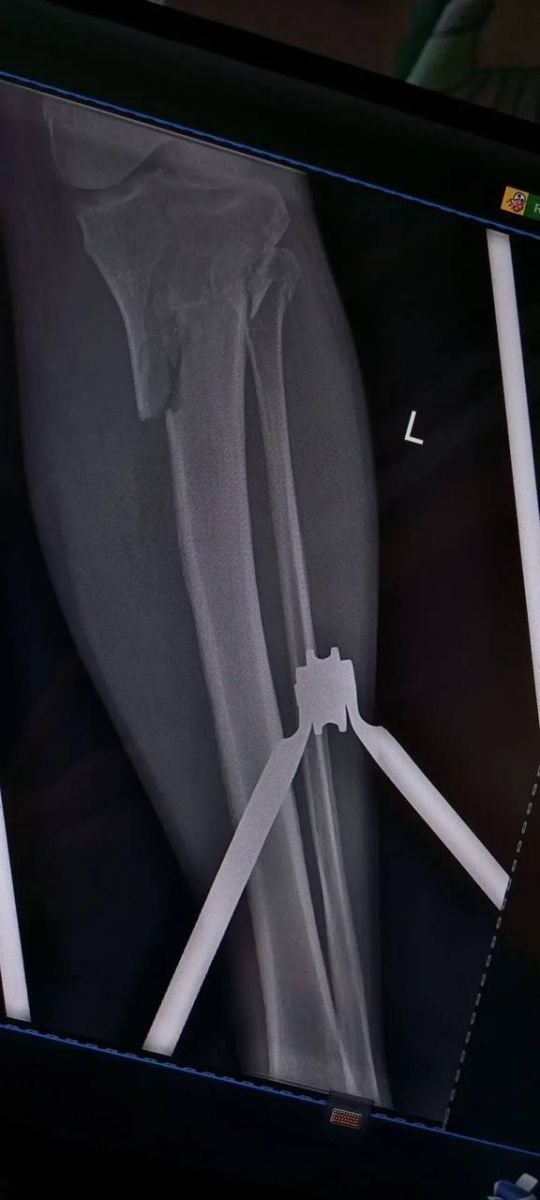

Врачи городской больницы № 4 «Липецк-Мед» провели сложнейшую 3-часовую операцию, чтобы спасти мужчину, который попал в страшное ДТП 25 февраля. При поступлении медики диагностировали у него внутрисуставные переломы верхних отделов обеих голеней – они были раздроблены.

Оперировала мужчину бригада во главе с завотделением травматологии Дмитрием Соколовым и травматологом Евгением Крюченковым. Хирурги приняли решение оперировать сразу обе ноги. Почти три часа врачи по кусочкам собирали разрушенные кости голеней.

Сейчас самое опасное позади, пациента уже перевели из реанимации в профильное отделение. Его состояние стабилизировалось. Теперь ему предстоят повторные операции, чтобы убрать скрепляющие конструкции после сращения костей, а затем долгий процесс восстановления и реабилитации.